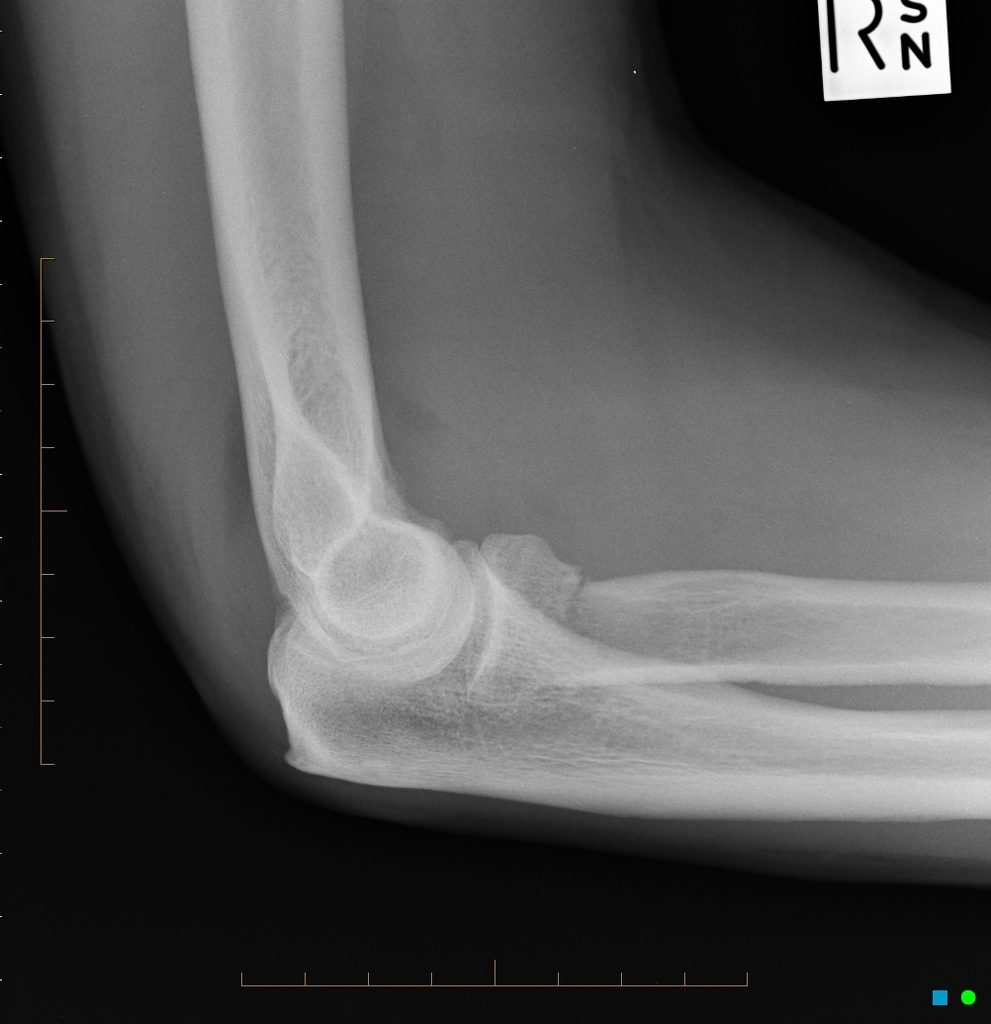

The elbow joint effusion is the Daddy Effusion for Radiographers. In the context of trauma, the presence of an elbow joint effusion is highly suggestive of intracapsular bony injury. Luckily, on a decent lateral projection, it’s easily spotted. We’re looking in two places to identify an elbow joint effusion; anteriorly and posteriorly to the distal humeral diaphysis.

Anteriorly, we’re looking for the “sail sign”.

The anterior fat pad is often visible on the normal elbow as a small, radiolucent focus tucked close to the anterior humeral cortex with its visible outline approximately following the line of the adjacent bone. It usually nestles within the coronoid fossa, the anterior depression in which the coronoid process of the ulna parks on full flexion of the elbow. When pushed up and out by an effusion, this fat pad is raised into a characteristically triangular shape to form the sail sign.

Posteriorly, we should see no such radiolucent focus.

The posterior fad pad sits inside a bony recess, the olecranon fossa, which is there to allow full extension of the elbow by housing the olecranon process. When pushed out by an effusion, the posterior fat pad sits proud of the olecranon fossa and becomes appreciable on a well-positioned lateral.